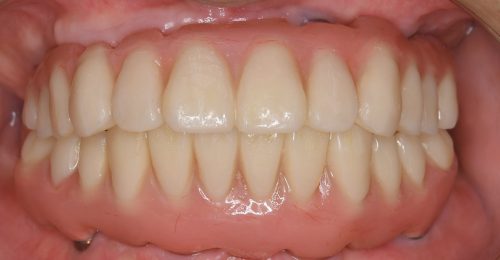

• オールオン4(上顎4本下顎4本)

術前

術後3年以上

年齢・性別 75歳・女性

治療期間 5ヶ月、通院回数18回

治療費用 5,492,080円(税込)

治療内容 1年前に作った入れ歯が痛くなり噛めない。バネも歯肉に刺さると来院。今回は入れ歯ではなくしっかり噛みたいということでオールオン4を希望。